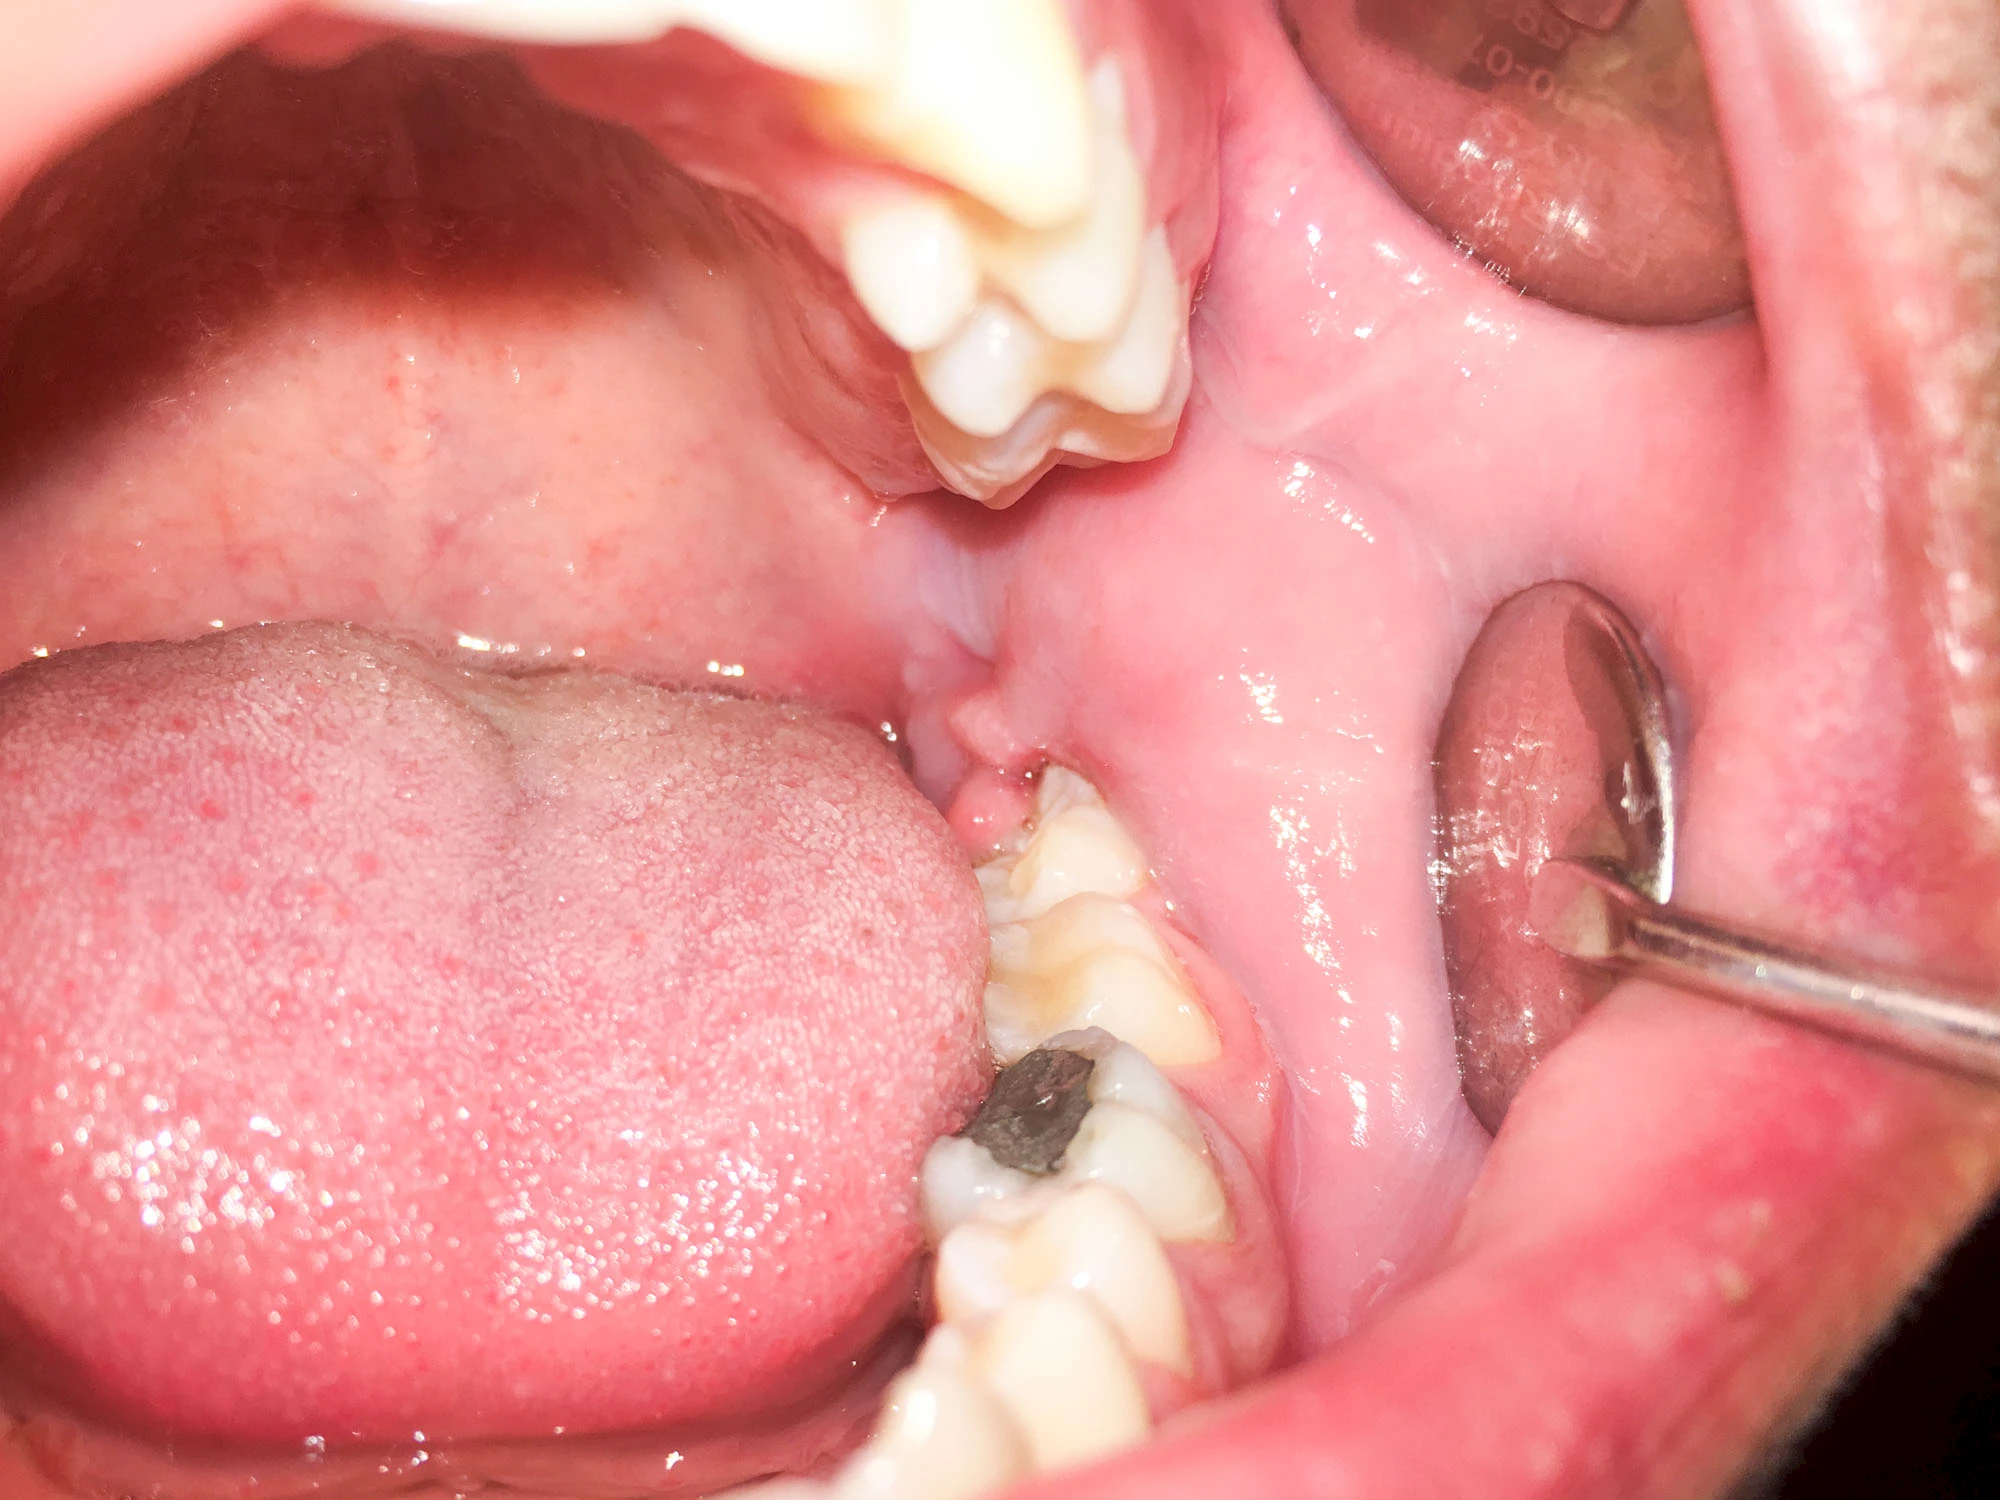

Sonderform: Schlupfwinkelinfektion

Im Laufe der menschlichen Entwicklung haben sich die Kiefer aufgrund unserer Nahrungsumstellung rückgebildet. Die Weisheitszähne haben daher oft keinen Platz mehr. Bei ca. 30 % der Menschen sind diese Zähne schon gar nicht mehr angelegt. Zum Teil liegen die Zähne versteckt (retiniert) im Kiefer und sind nicht sichtbar. Hin und wieder brechen die Zähne zwar durch die Schleimhaut, aber nicht vollständig – es handelt sich um einen erschwerten Zahndurchbruch (dentitio difficilis). Dann sind die Zähne noch teilweise bedeckt von einer "Schleimhautkapuze". Gehen hier Speisereste und Bakterien unter die Schleimhautkapuze kann sich eine sogenannte Schlupfwinkelinfektion bilden. Diese Entzündungen treten spontan auf, sind häufig sehr schmerzhaft und die Mundöffnung ist eingeschränkt. Hier ist umgehend der Zahnarzt zu kontaktieren.